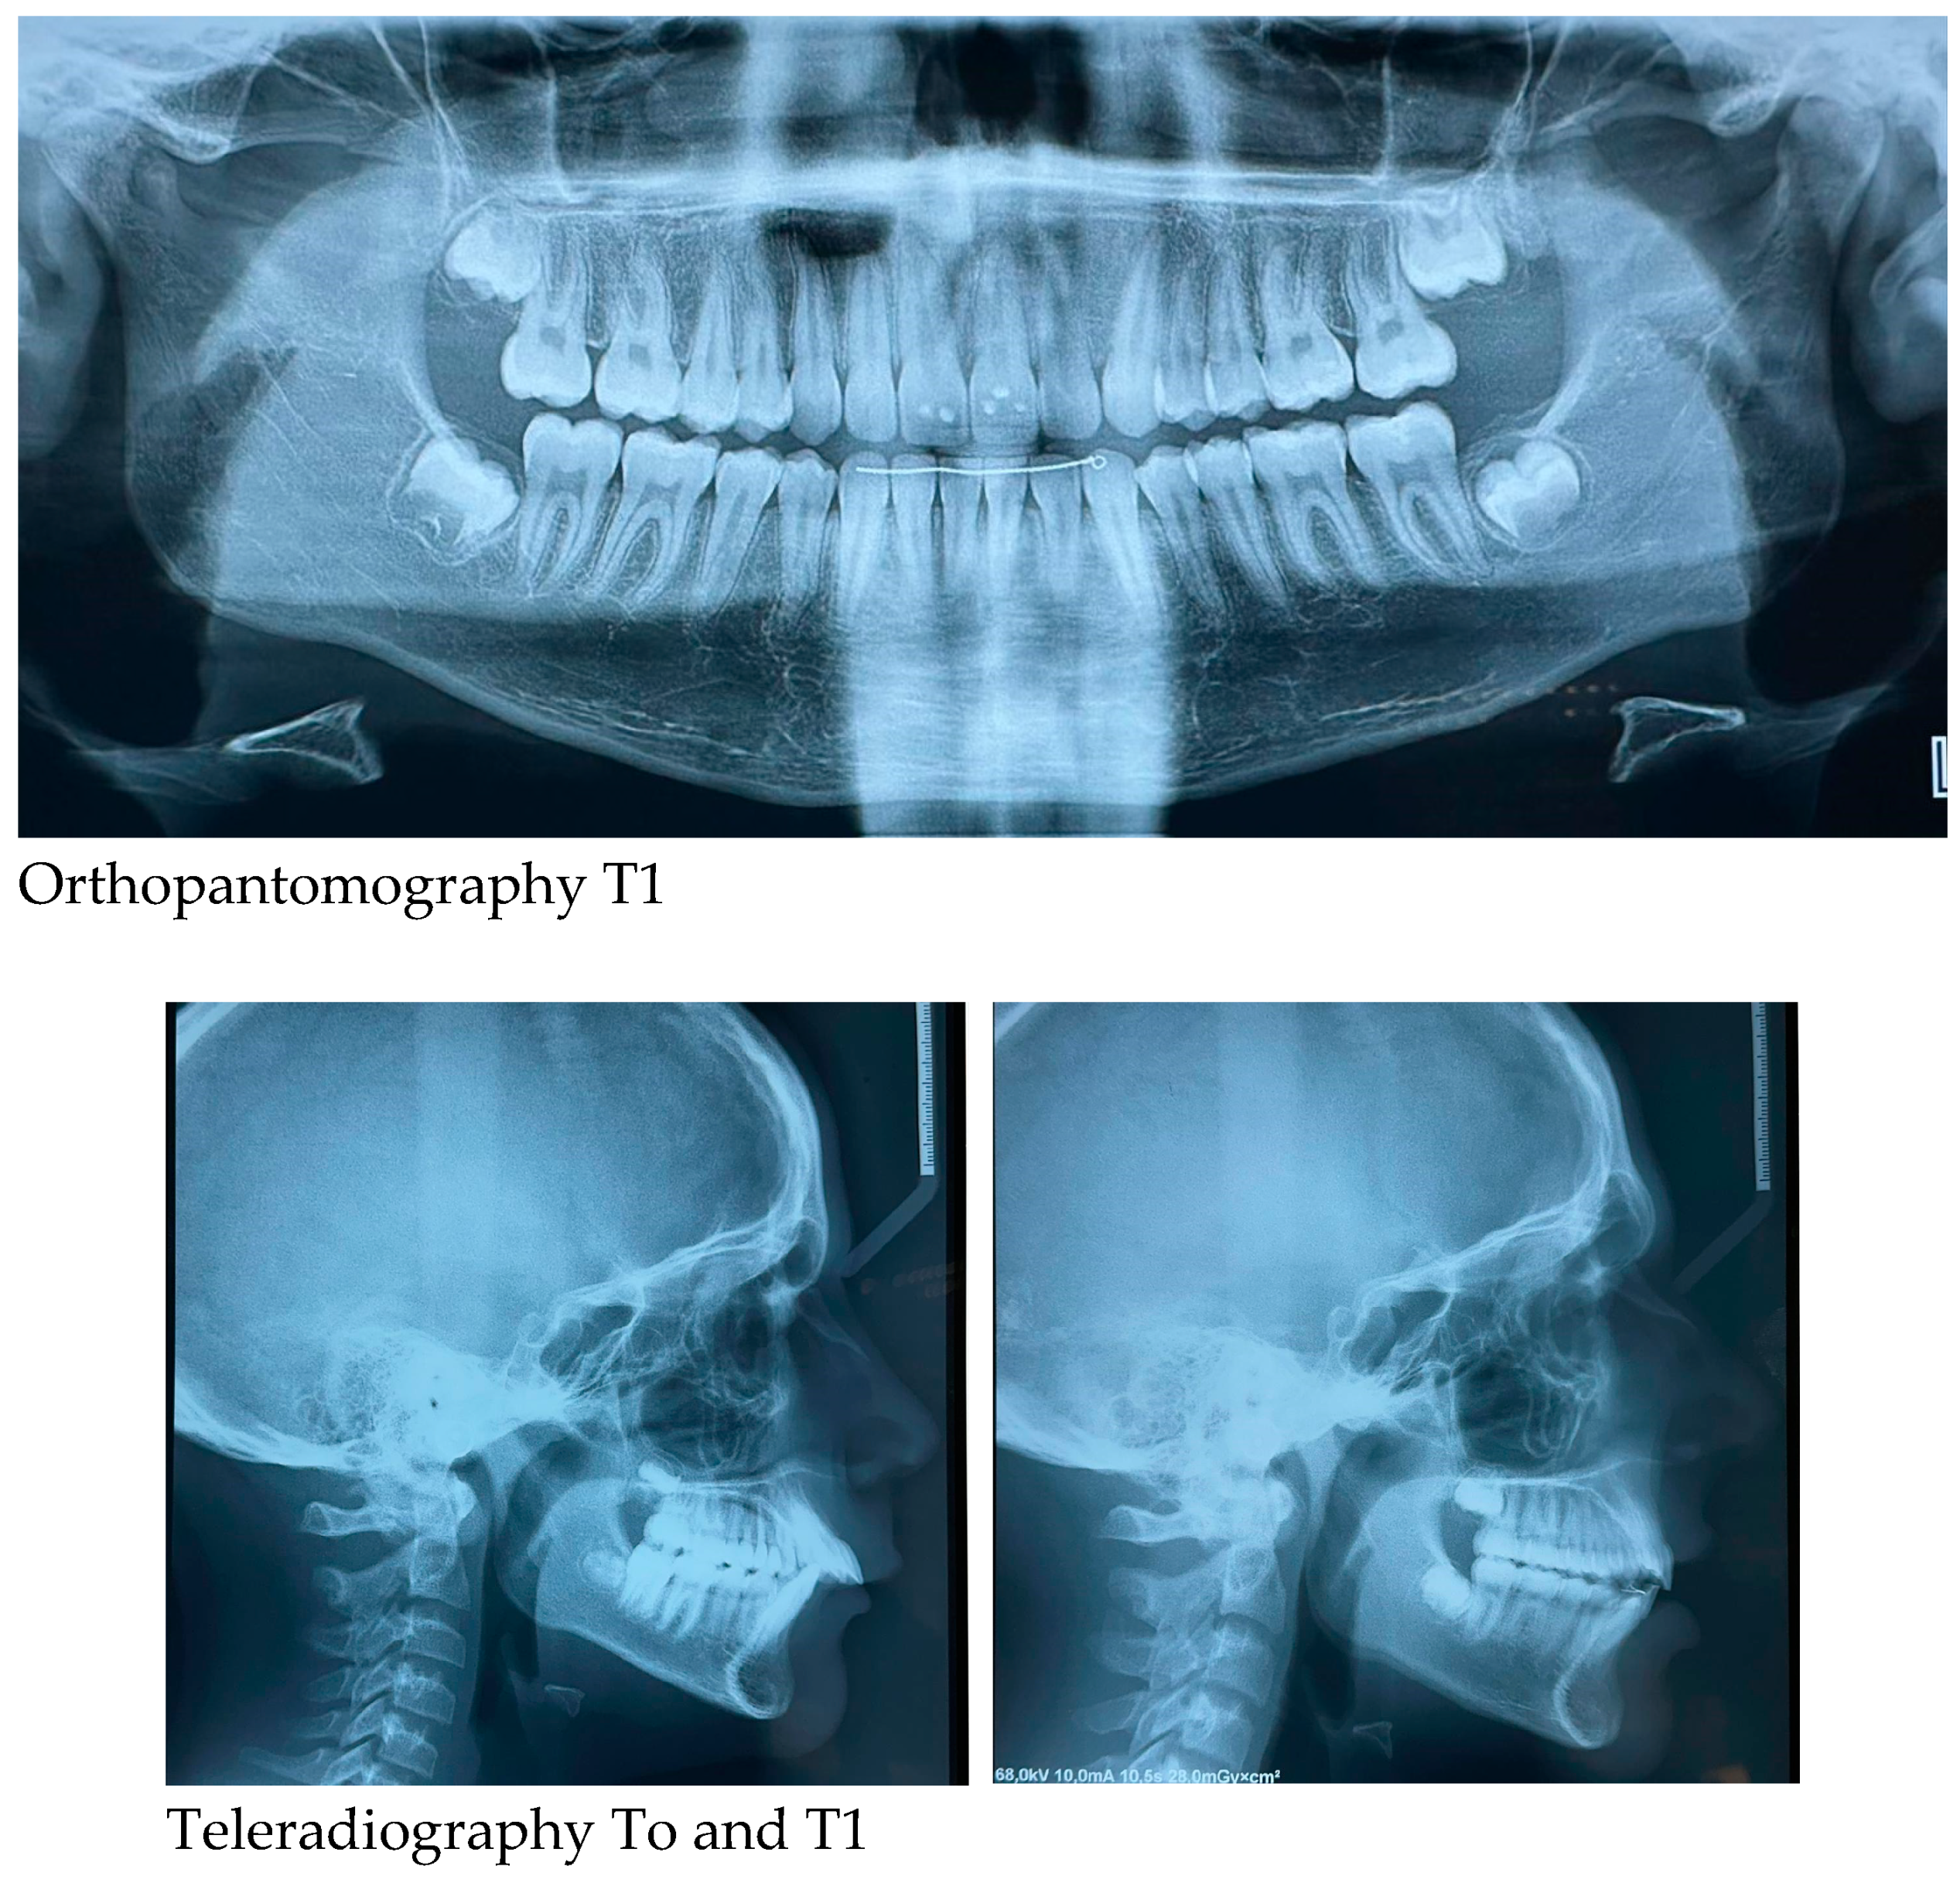

2.3. Initial and Post-Treatment Records

Orthopantomography of the dental arches and lateral skull teleradiography taken before (T0-at the start of treatment) and at the end of Herbst-RPE therapy (T1-after removal of braces) were evaluated. The subject was positioned in the natural head position, with the teeth in centric occlusion and with the lips slightly closed for lateral cephalometric radiographs.

Radiographs such as orthopantomography and lateral skull teleradiography are provided. The cephamolecular analysis shows some changes: improvement of the Wits index, growth of the mandibular ramus while keeping the position of the lower incisors almost unchanged (

Table 1).